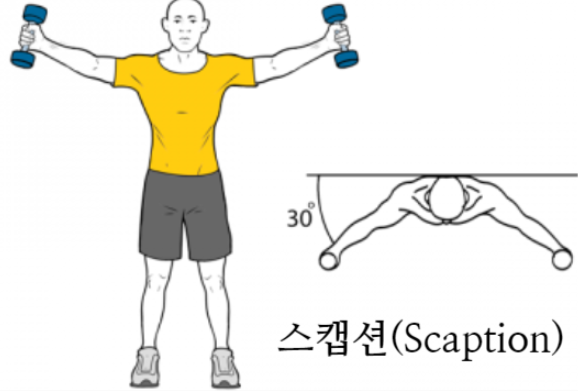

일반적으로 팔을 벌리는(팔벌려 뛰기 동작) 외전과 다르게 견갑골 관절면(Scapular plane)을 따라서 팔을 들어올리는 것을 스캡션(Scaption) 이라고 하는데요.

스캡션(Scaption)시에는 해부적구조상 극상근의 결의 방향과 힘의 방향이 그대로 일치합니다. 따라서 초음파로 동적 검사(Dynamic test) 시 극상근의 파열을 더 잘보려고 할 때 스캡션(Scaption)을 하라고 하면서 저항을 주면서(Full can test와 동일) 극상근의 파열부가 벌어지는것을 초음파로 확인해줄 때 사용합니다.